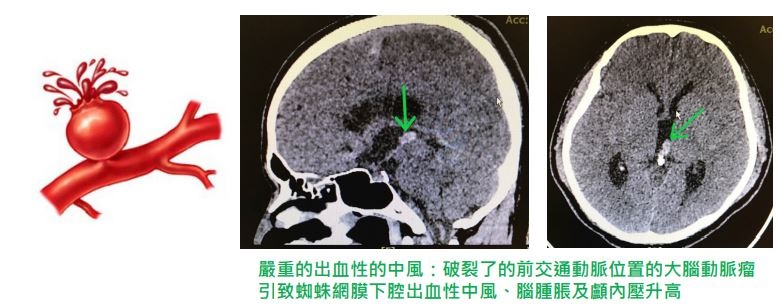

破裂性動脈瘤

破裂出血的動脈瘤稱之為「破裂性動脈瘤」。當動脈瘤破裂時,血液流入腦組織周圍的腦脊液中,這類型的出血稱之為蛛網膜下腔出血。動脈瘤破裂往往會引起突發的劇烈頭痛,常被描述成「一生當中最嚴重的頭痛」,還有的是嚴重的噁心和嘔吐,頸項強直甚至昏迷等症狀。

雖然動脈瘤破裂出血的過程僅僅持續數秒鐘,但卻能帶來一系列嚴重的後果。出血會損傷腦細胞,壓迫腦組織或引起血管狹窄(又稱為血管痙攣)。當動脈痙攣引起腦組織缺血時就導致了中風。腦脊液中出現大量血液時會引起腦脊液流速減慢甚至停滯,從而引起腦積水。